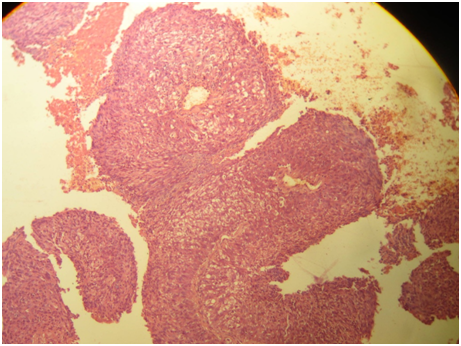

Mr RAV. 53 years old, no smoking was hospitalized for progressive worsening of dyspnea lasting for 6 months, accompanied by chest pain basi-left. In the interview we noted a notion regularly taking a decoction of clinical médicinales. L'examen virtues plants entering found an alteration of the general status (PS=3 according to WHO), a left pulmonary syndrome without condensation fever. Radiography of thorax face showed pleural thickening picture left scalloped. Chest CT (Figure 1) confirmed the pleural lesions secondary look and abdominopelvic CT scan for staging (Figure 2) found a retroperitoneal mass compatible of renal tumor primitive right. Biologically, there was a LDH assay was raised to 1423 IU/ml (5 times normal). Histological examination of a biopsy transthoracic puncture confirmed the location of a secondary urothelial carcinoma at the pleura (pT4N2M1) (Figure 3). Our patient had received a course of BCG instillation Pasteur by percutaneous nephrostomy and the tear-X (thoracic drainage system) and died after three months of decline following the natural evolution of the tumor.

Figure 3 M/E, HE*100 urothelial carcinoma infiltrating the pleura.